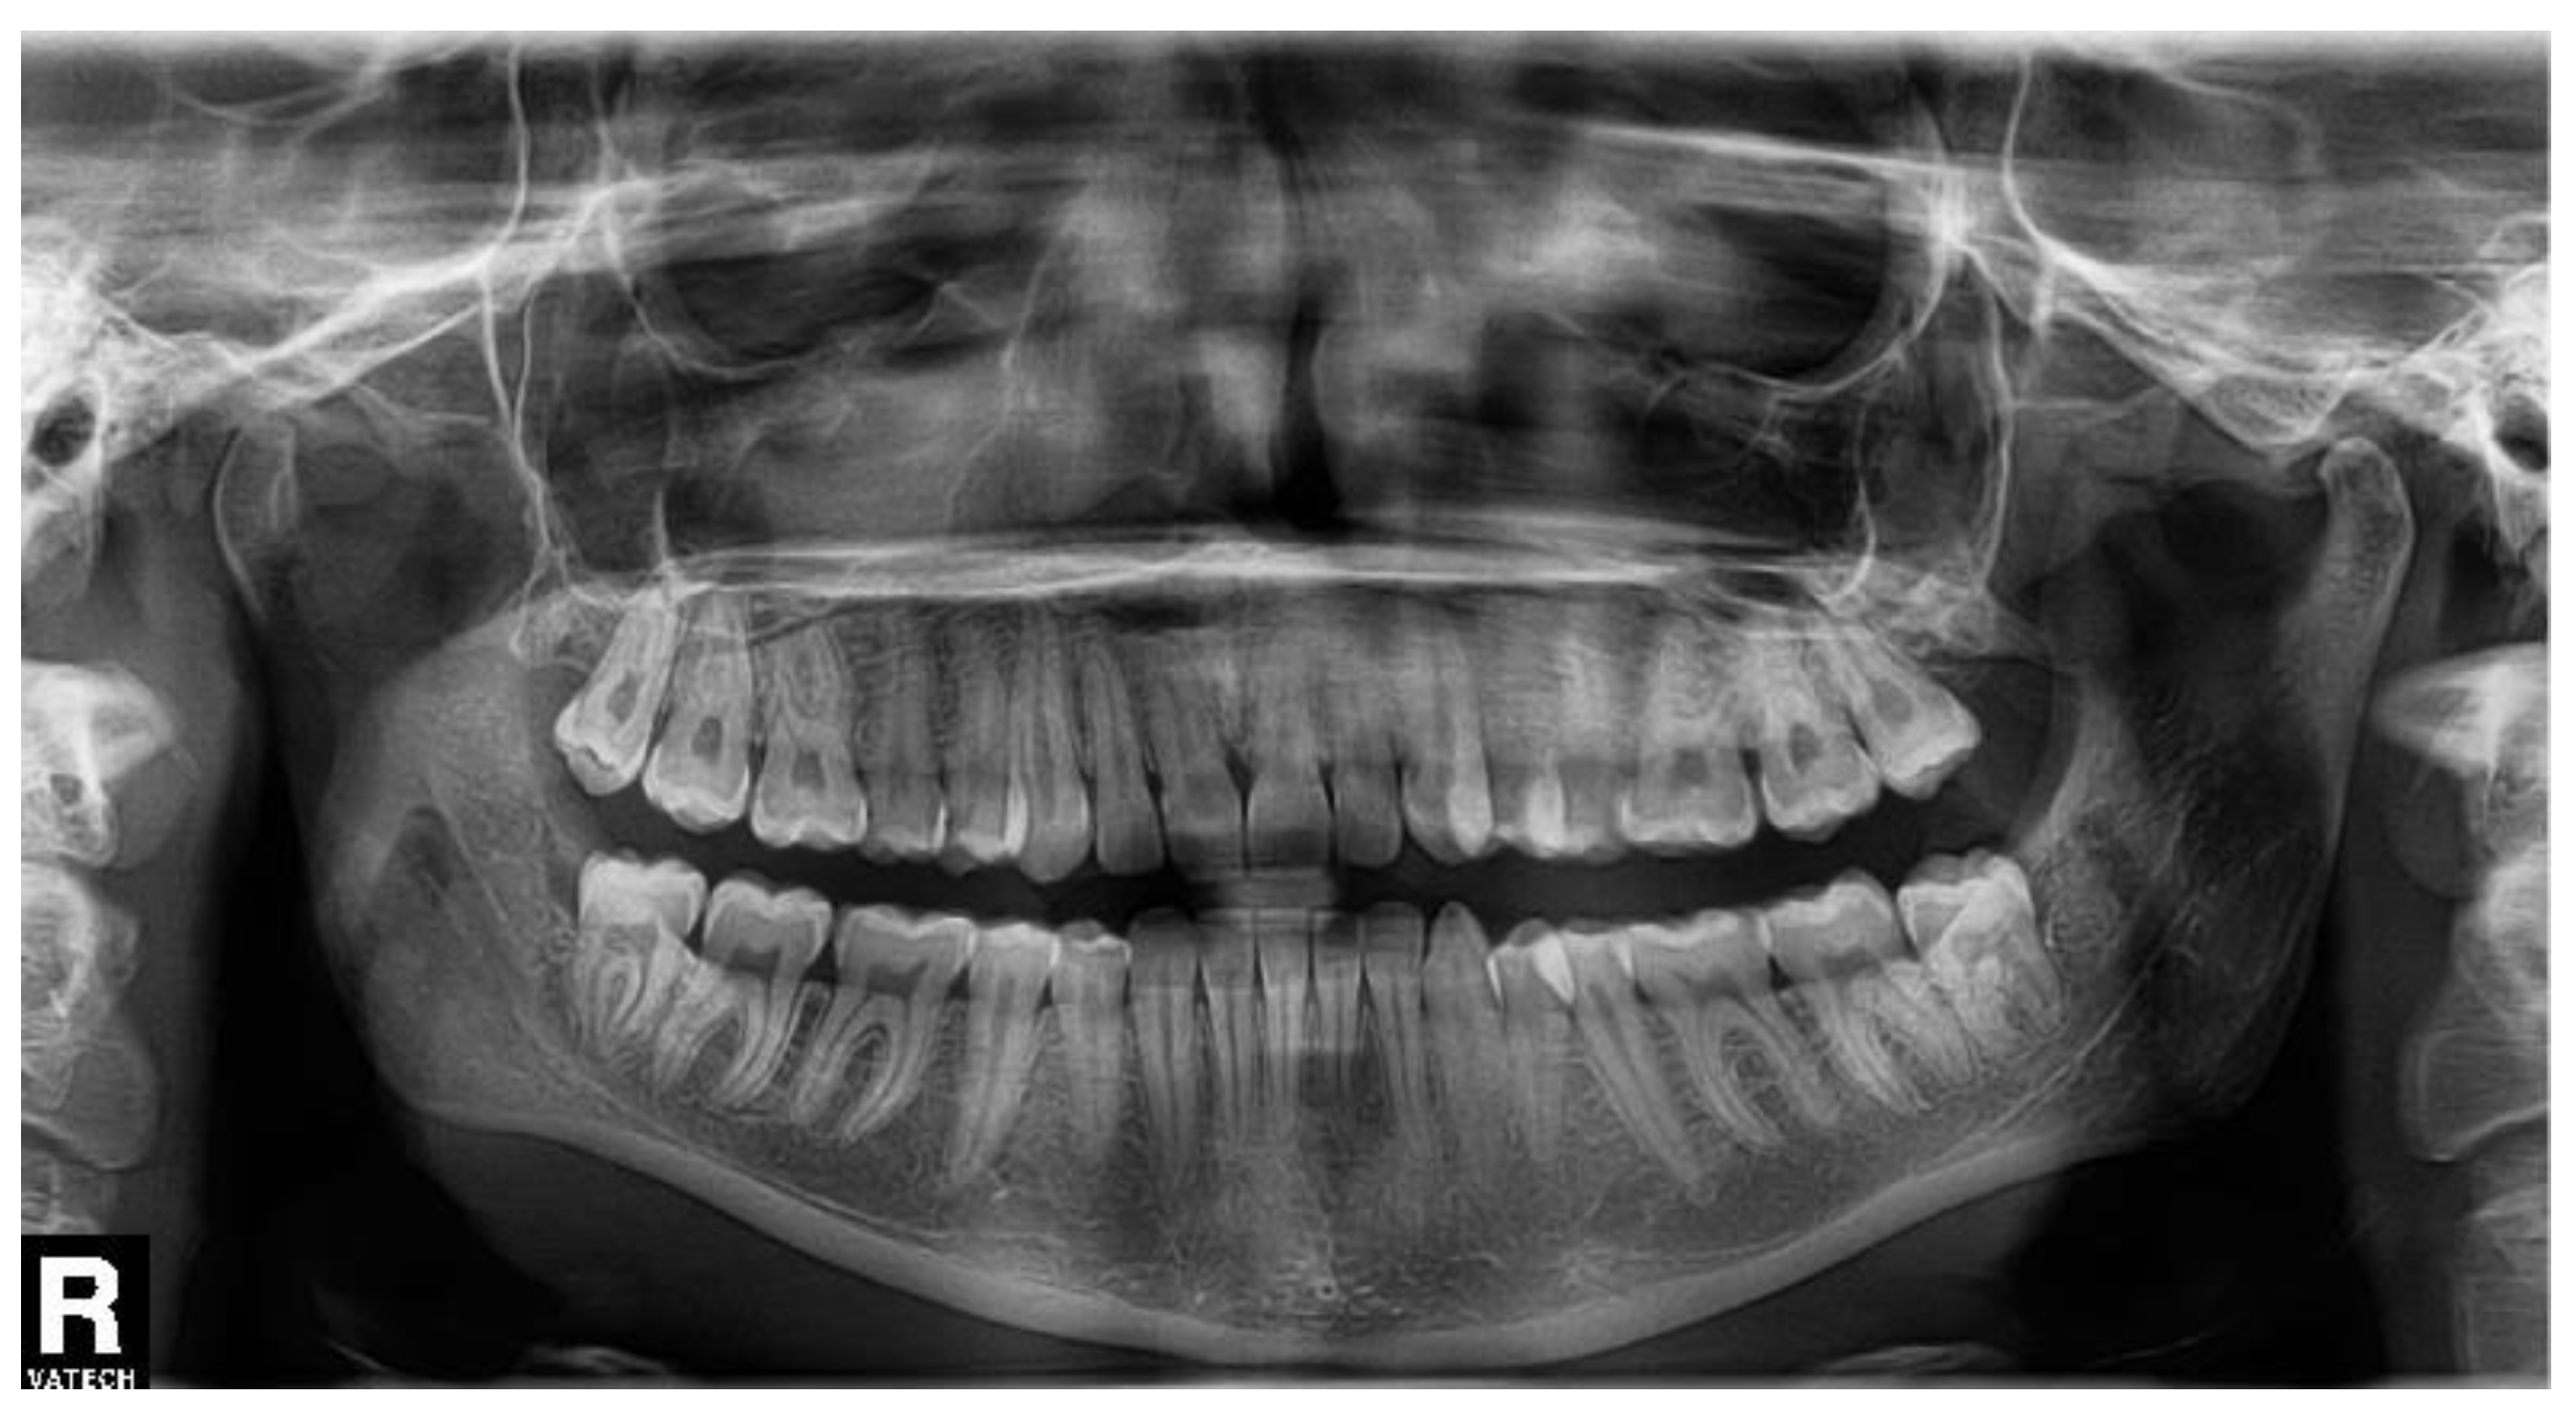

A woman of age 48 years had her semi-impacted tooth No. 38 extracted for recurrent pericoronitis. The OPG (Figure 3) showed a semilunar burnout distally from the tooth crown. The patient did not have any general disease, medication, or allergy, and she did not smoke. There was no pain nor swelling prior to the transalveolar extraction, which lasted 10 min. No antibiotics were prescribed.

Figure 3. The orthopantomogram of the patient 2. Tooth No. 38 is in normal position, slightly distally inclined, with a semilunar burnout distally. The OPG was not taken at our department.